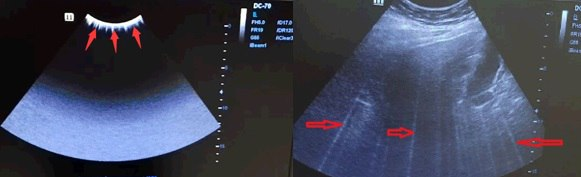

Белые линии в области визуализации

⚠️ Проблема: При включенной гармонике в области изображения иногда могут «мигать» белые линии. Они могут исчезнуть при включении и выключении "сток-кадр". На рисунках ниже показан пример.

3.png

💡 Причина: Программируемая логическая матрица TR-FPGA на плате TR64 вышла из строя, что приводит к сбою. Сбой происходит только при включенной гармонике. Вы можете попробовать выключить гармонику, чтобы понять, остается ли проблема после выключения гармоники.

✅ Решение: Программируемая логическая матрица TR-FPGA на плате TR64 в аппарате Mindray DC-70 была изменена на ECN (EGD019F). При столкновении с такой проблемой на DC-70, обновите программное обеспечение Doppler до версии V01 08 01 или выше.